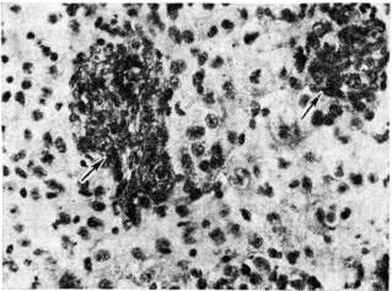

НейробластомаНейробластома (neuroblastoma; греческий neuron нерв + blastos росток -oma) — злокачественная дизонтогенетическая опухоль, состоящая из незрелых клеток ганглиозно-клеточного ряда. Классификация ганглиозно-клеточных опухолей трудна, так как в одной и той же опухоли нередко определяются элементы различной степени зрелости. В связи с этим Уиллис (R. Willis) предлагает пользоваться термином «Нейробластома» как обобщающим и наиболее простым. Нейробластома встречаются редко, преимущественно в детском и юношеском возрасте. По локализации различают Нейробластома головного мозга и Нейробластома, исходящие из элементов симпатической части высшая нервная система Патологическая анатомия. Из Нейробластома головного мозга описаны Нейробластома области серого бугра и третьего желудочка, белого вещества полушарий большого мозга, мозжечка. Макроскопически опухоль имеет вид узла серо-розового цвета диаметром от 1 до 1,5 сантиметров на разрезе ткань опухоли пористая, нередко с кистами. Микроскопически Нейробластома состоит из довольно плотно примыкающих друг к другу клеток, местами с образованием розеток, состоящих из безотростчатых аполярных нейробластов, выявляемых при импрегнации по Бильшовскому — Грос — Лаврентьеву. Опухолевые клетки представлены нейробластами различной степени зрелости, вплоть до зрелых ганглиозных клеток с нисслевской зернистостью в цитоплазме. Ядра опухолевых клеток пузырьковидные, различны по величине, с чётким темно-окрашенным ядрышком (рисунок 1). Соединительнотканная строма развита слабо. В ткани опухоли встречаются митозы, некрозы. Рост Нейробластома инфильтративный с неглубоким прорастанием окружающей ткани. Нейробластома симпатической части век н. с. исходят из крупных симпатических узлов и мелких интрамуральных ганглиев внутренних органов, а также из мозгового слоя надпочечников. Макроскопически они имеют вид узлов различной величины и окраски. В ткани опухоли встречаются очаги некроза. По степени зрелости среди Нейробластома симпатической части век н. с. различают симпатогониомы и симпатобластомы. Симпатогониома — наиболее злокачественная, незрелая, примитивная опухоль; встречается у новорожденных и в раннем детском возрасте. Опухолевые клетки — со скудной цитоплазмой и округлым темным ядром, напоминающим лимфоцит. Иногда встречаются псевдорозетки (рисунок 2). Эти клетки происходят из примитивных клеток — симпатогоний, отсюда термин «симпатогониома». Симпатобластома — более дифференцированная опухоль. Она содержит отростчатые нейробласты с крупными телами овальной, вытянутой иди полигональной формы, с пузырьковидным ядром, содержащим глыбки хроматина в виде спиц в колесе. Располагаются клетки плотно, иногда в виде тяжей, колонн, пучков. В ряде случаев встречаются ложные или истинные розетки (рисунок 3), некротические очаги. Разграничить симпатогониомы и симпатобластомы не всегда удаётся: такие опухоли, согласно номенклатуре ВОЗ, обозначают как нейробластомы. Клиническая картина. Нейробластома— злокачественные опухоли, дающие метастазы в пределах центральная нервная система и за её пределами, размеры метастазов нередко превышают размеры основного опухолевого узла. Эти опухоли часто рецидивируют. Клинические, картина Нейробластома головного мозга зависит от локализации опухоли и характера метастазирования (смотри полный свод знаний Головной мозг, опухоли). Нейробластома симпатической части век н. с. резко злокачественны, дают метастазы во внутренние органы и кости грудной клетки, черепа (симпатогониомы в 80% случаев). Клинические, картина весьма разнообразна. В частности, описаны две своеобразные формы симпатогониомы, происходящей из мозгового вещества надпочечников, известные как синдром Пеппера и синдром Гетчинсона. При синдроме Пеппера (описан в 1901 г.) опухоль метастазирует по лимфатических, путям преимущественно в органы брюшной полости. В раннем детском или грудном возрасте, иногда с рождения, отмечается резко прогрессирующая гепатомегалия, прощупываются подкожные узелки метастазов. Быстро наступают анемия, кахексия, резко ускоряется РОЭ. Течение характеризуется обострениями с периодами лихорадки. При синдроме Гетчинсона (описан в 1907 г.) опухоль метастазирует преимущественно в кости (основание черепа, длинные трубчатые кости). |